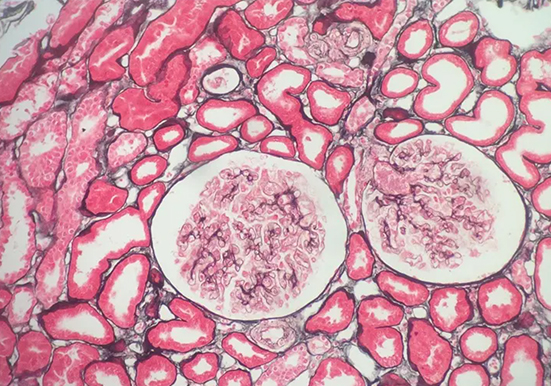

瑞士吉姆萨染色

以下是关于瑞士吉姆萨染色的详细介绍:基本原理吉姆萨染液由天青、伊红等成分组成。其染色原理基于细胞内不同物质的酸碱性质差异。细胞内的嗜酸性物质,如碱性蛋白质,与酸···

甲苯胺蓝染色

以下是关于甲苯胺蓝染色的详细介绍:染色原理化学结构基础:甲苯胺蓝属于醌亚胺染料类,含有两个发色团(胺基和醌型苯环)和两个助色团。助色团促使染料电离成盐类,帮助发···

肥大细胞染色

肥大细胞染色是一种病理学检查方法,用于检测组织中肥大细胞的数量、分布和形态等情况,对多种疾病的诊断和研究具有重要意义。以下是一些常见的肥大细胞染色方法:甲苯胺蓝···

刚果红染色

刚果红染色是一种常用的生物染色方法,以下是关于它的详细介绍:基本信息染料性质:刚果红是一种经典的酸性染料,化学式为 C32H22N6Na2O6S2,是一种棕红色粉末,能溶于水和···